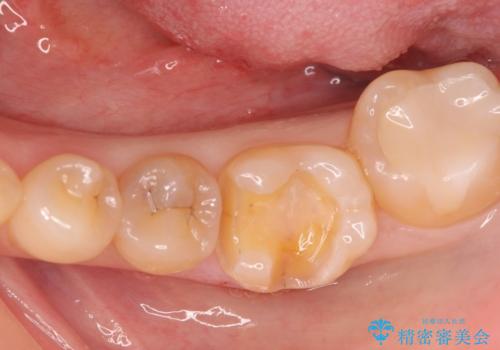

メタルインレーをセラミックインレーに。

- メタルインレーをセラミックインレーに変えたいとの事で来院。

メタルインレーを外し、拡大鏡下でう蝕がないことを確認して

セラミックインレー(e-maxインレー)にて治療しました。